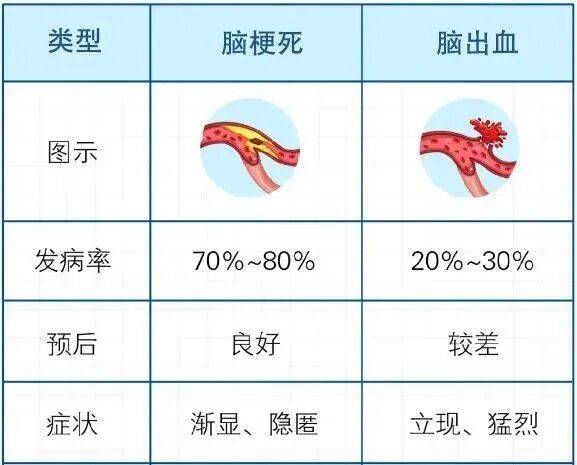

脑梗高发季到了!有3种不舒服,千万别大意

秋意渐浓,气温渐低,心脑血管疾病又到了高发季节。多位医生表示,近期门诊中脑梗等急症的就诊量,呈现出上升趋势。

脑梗起病急、进展快,一旦发作,每延误1分钟的救治,就有约190万个脑细胞死亡。若错过4.5小时的黄金治疗窗口,可能留下偏瘫、失语等后遗症。

脑血管破了或堵了,统称为脑卒中(cù zhòng),又叫中风,包括脑梗死和脑出血。

上海交通大学医学院附属第九人民医院神经外科主任医师楚胜华表示,秋冬尤其是换季的时候,是脑梗的高发时节,数据显示,秋冬脑梗的复发率比春夏高出30%以上,这与气候特点密切相关。